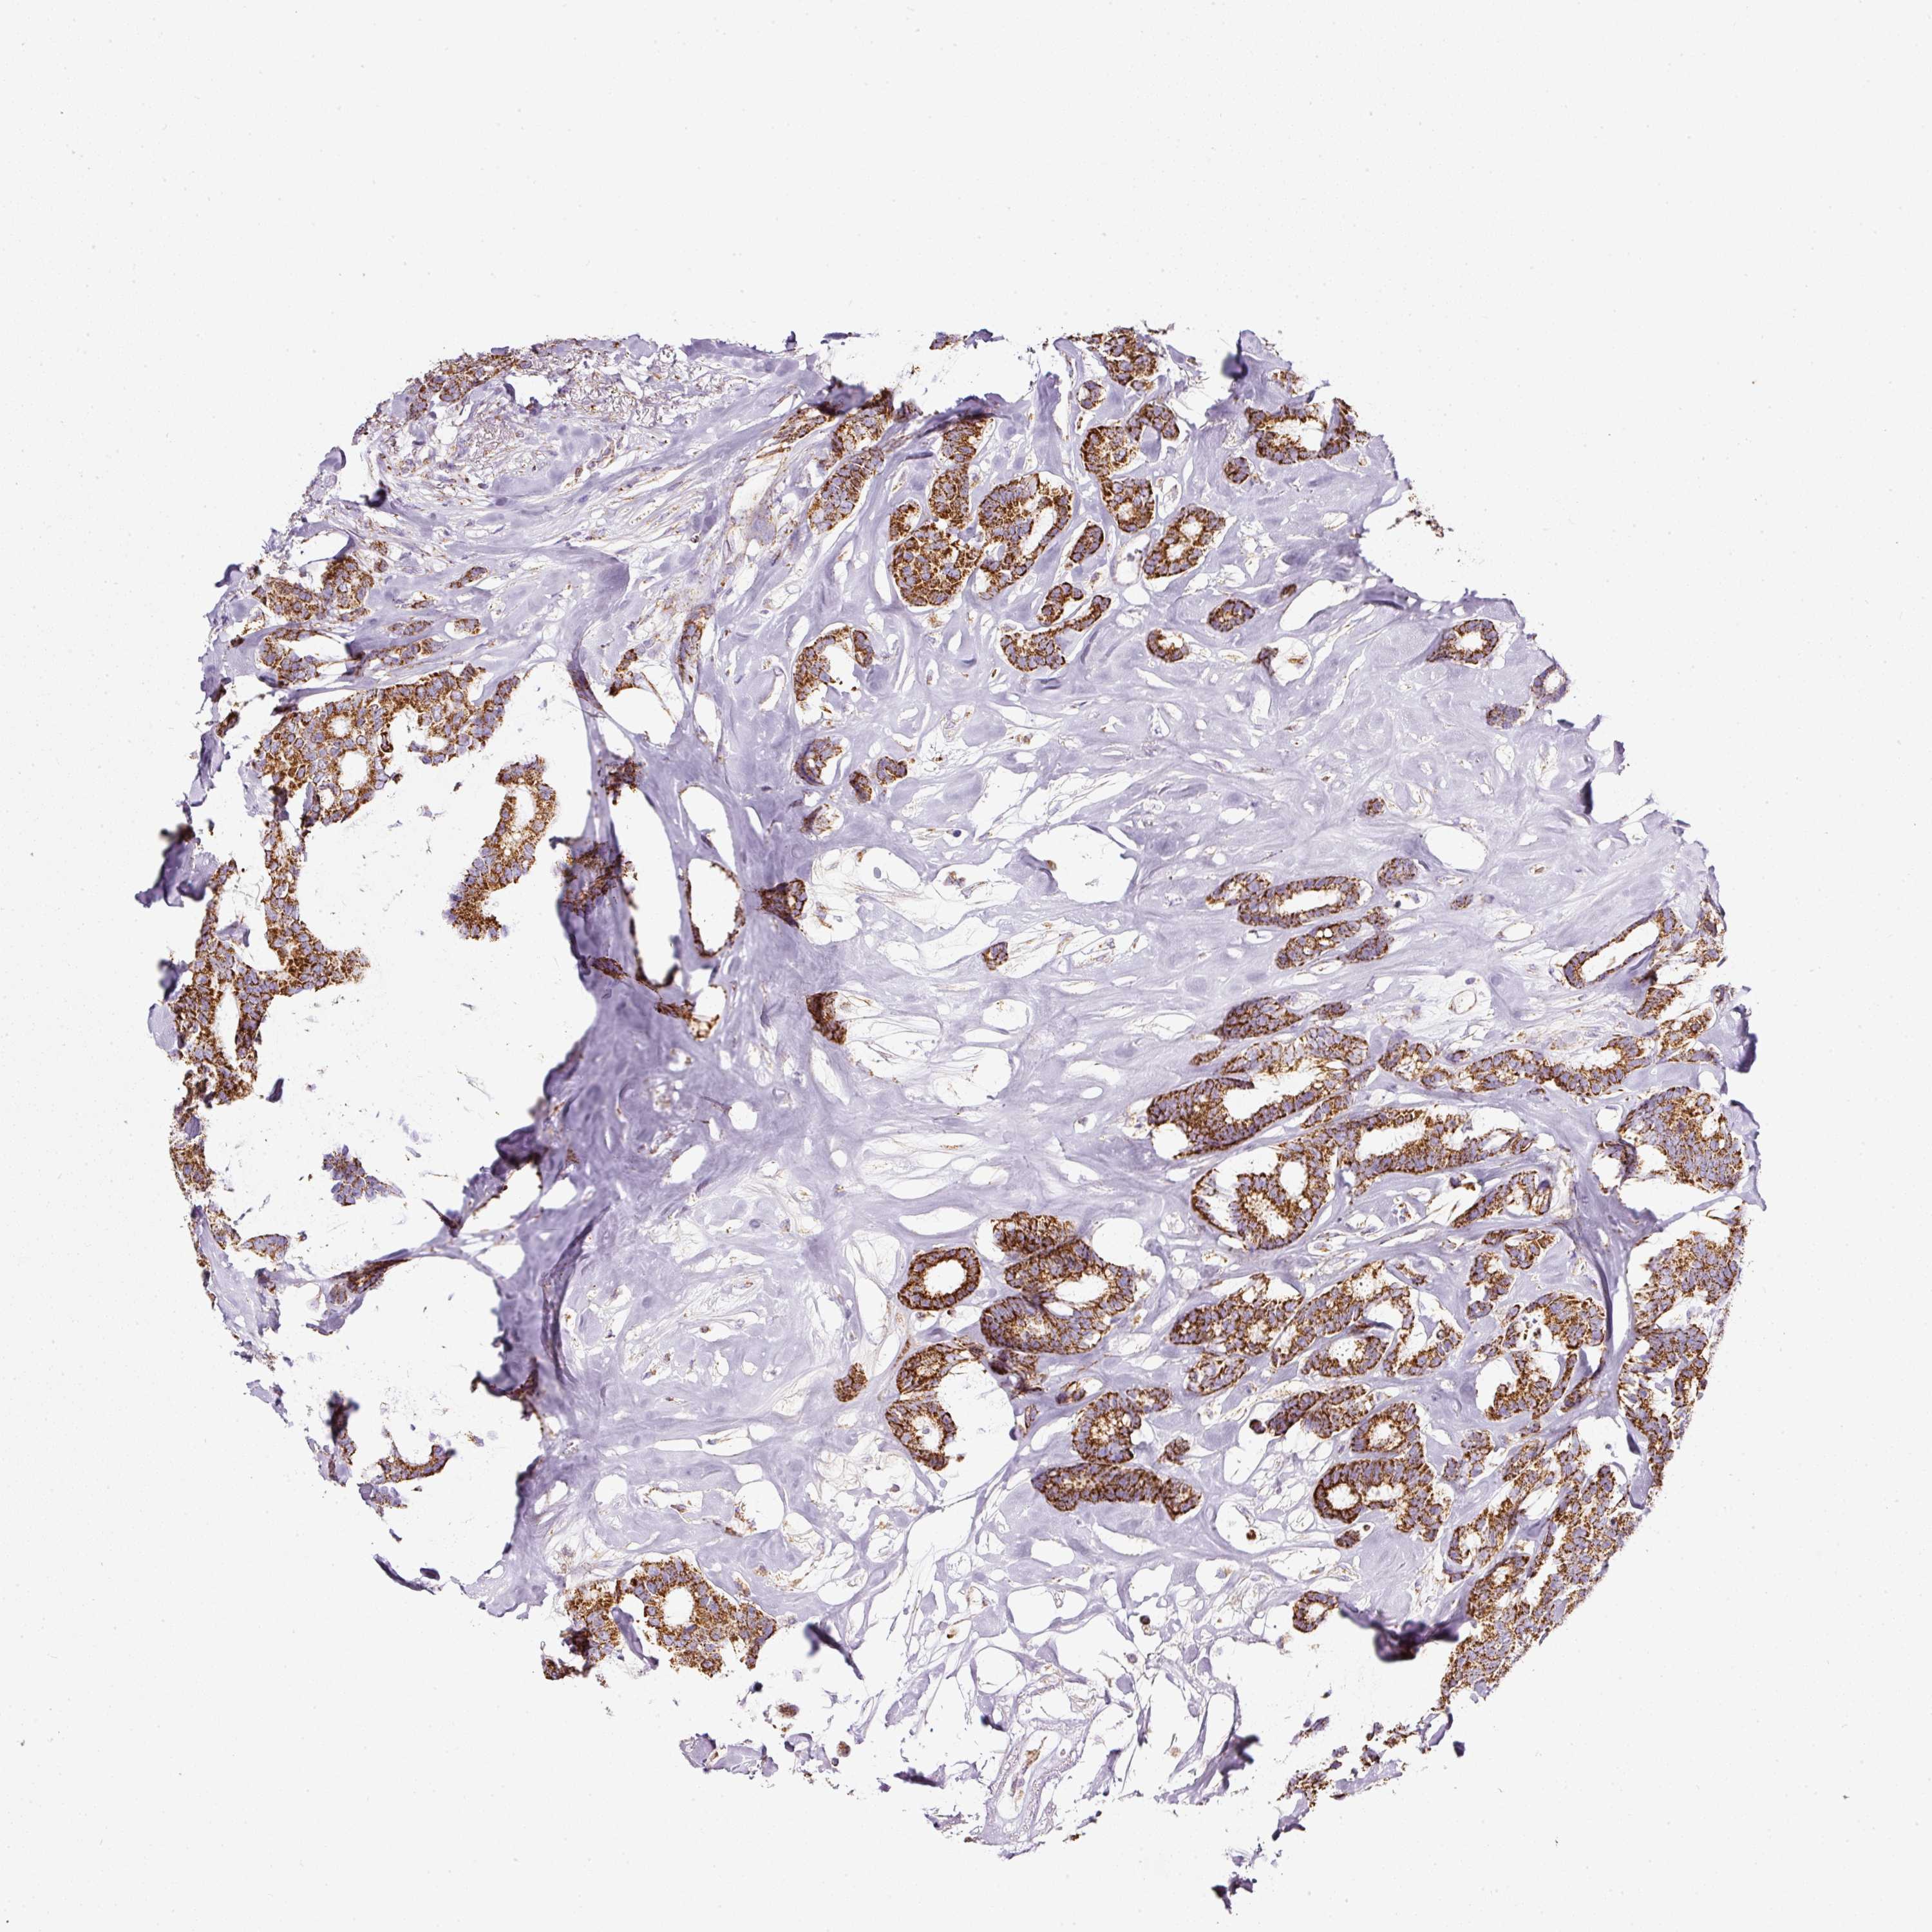

CANCER BREAST CANCER Show tissue menu

BRCA TCGA BRCA VALIDATION PROTEIN EXPRESSION